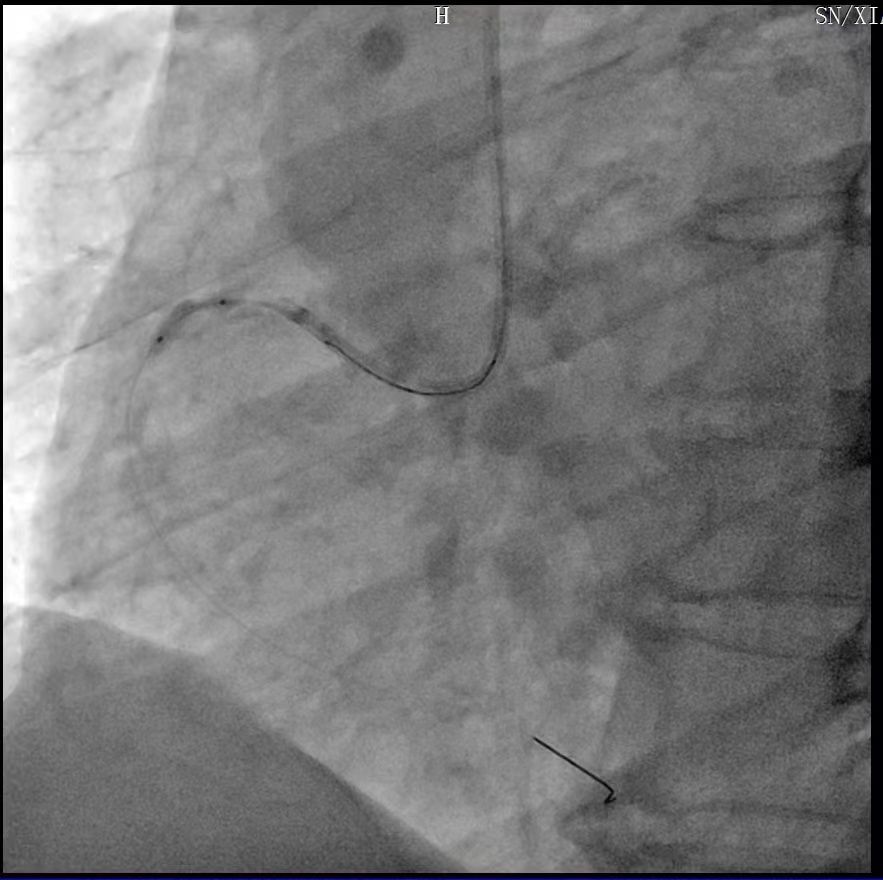

导管支持下通过OCT导管

OCT-冠脉造影融合技术评价钙化病变并实时定位,提示右冠脉近中段存在重度360°环状钙化狭窄病变。